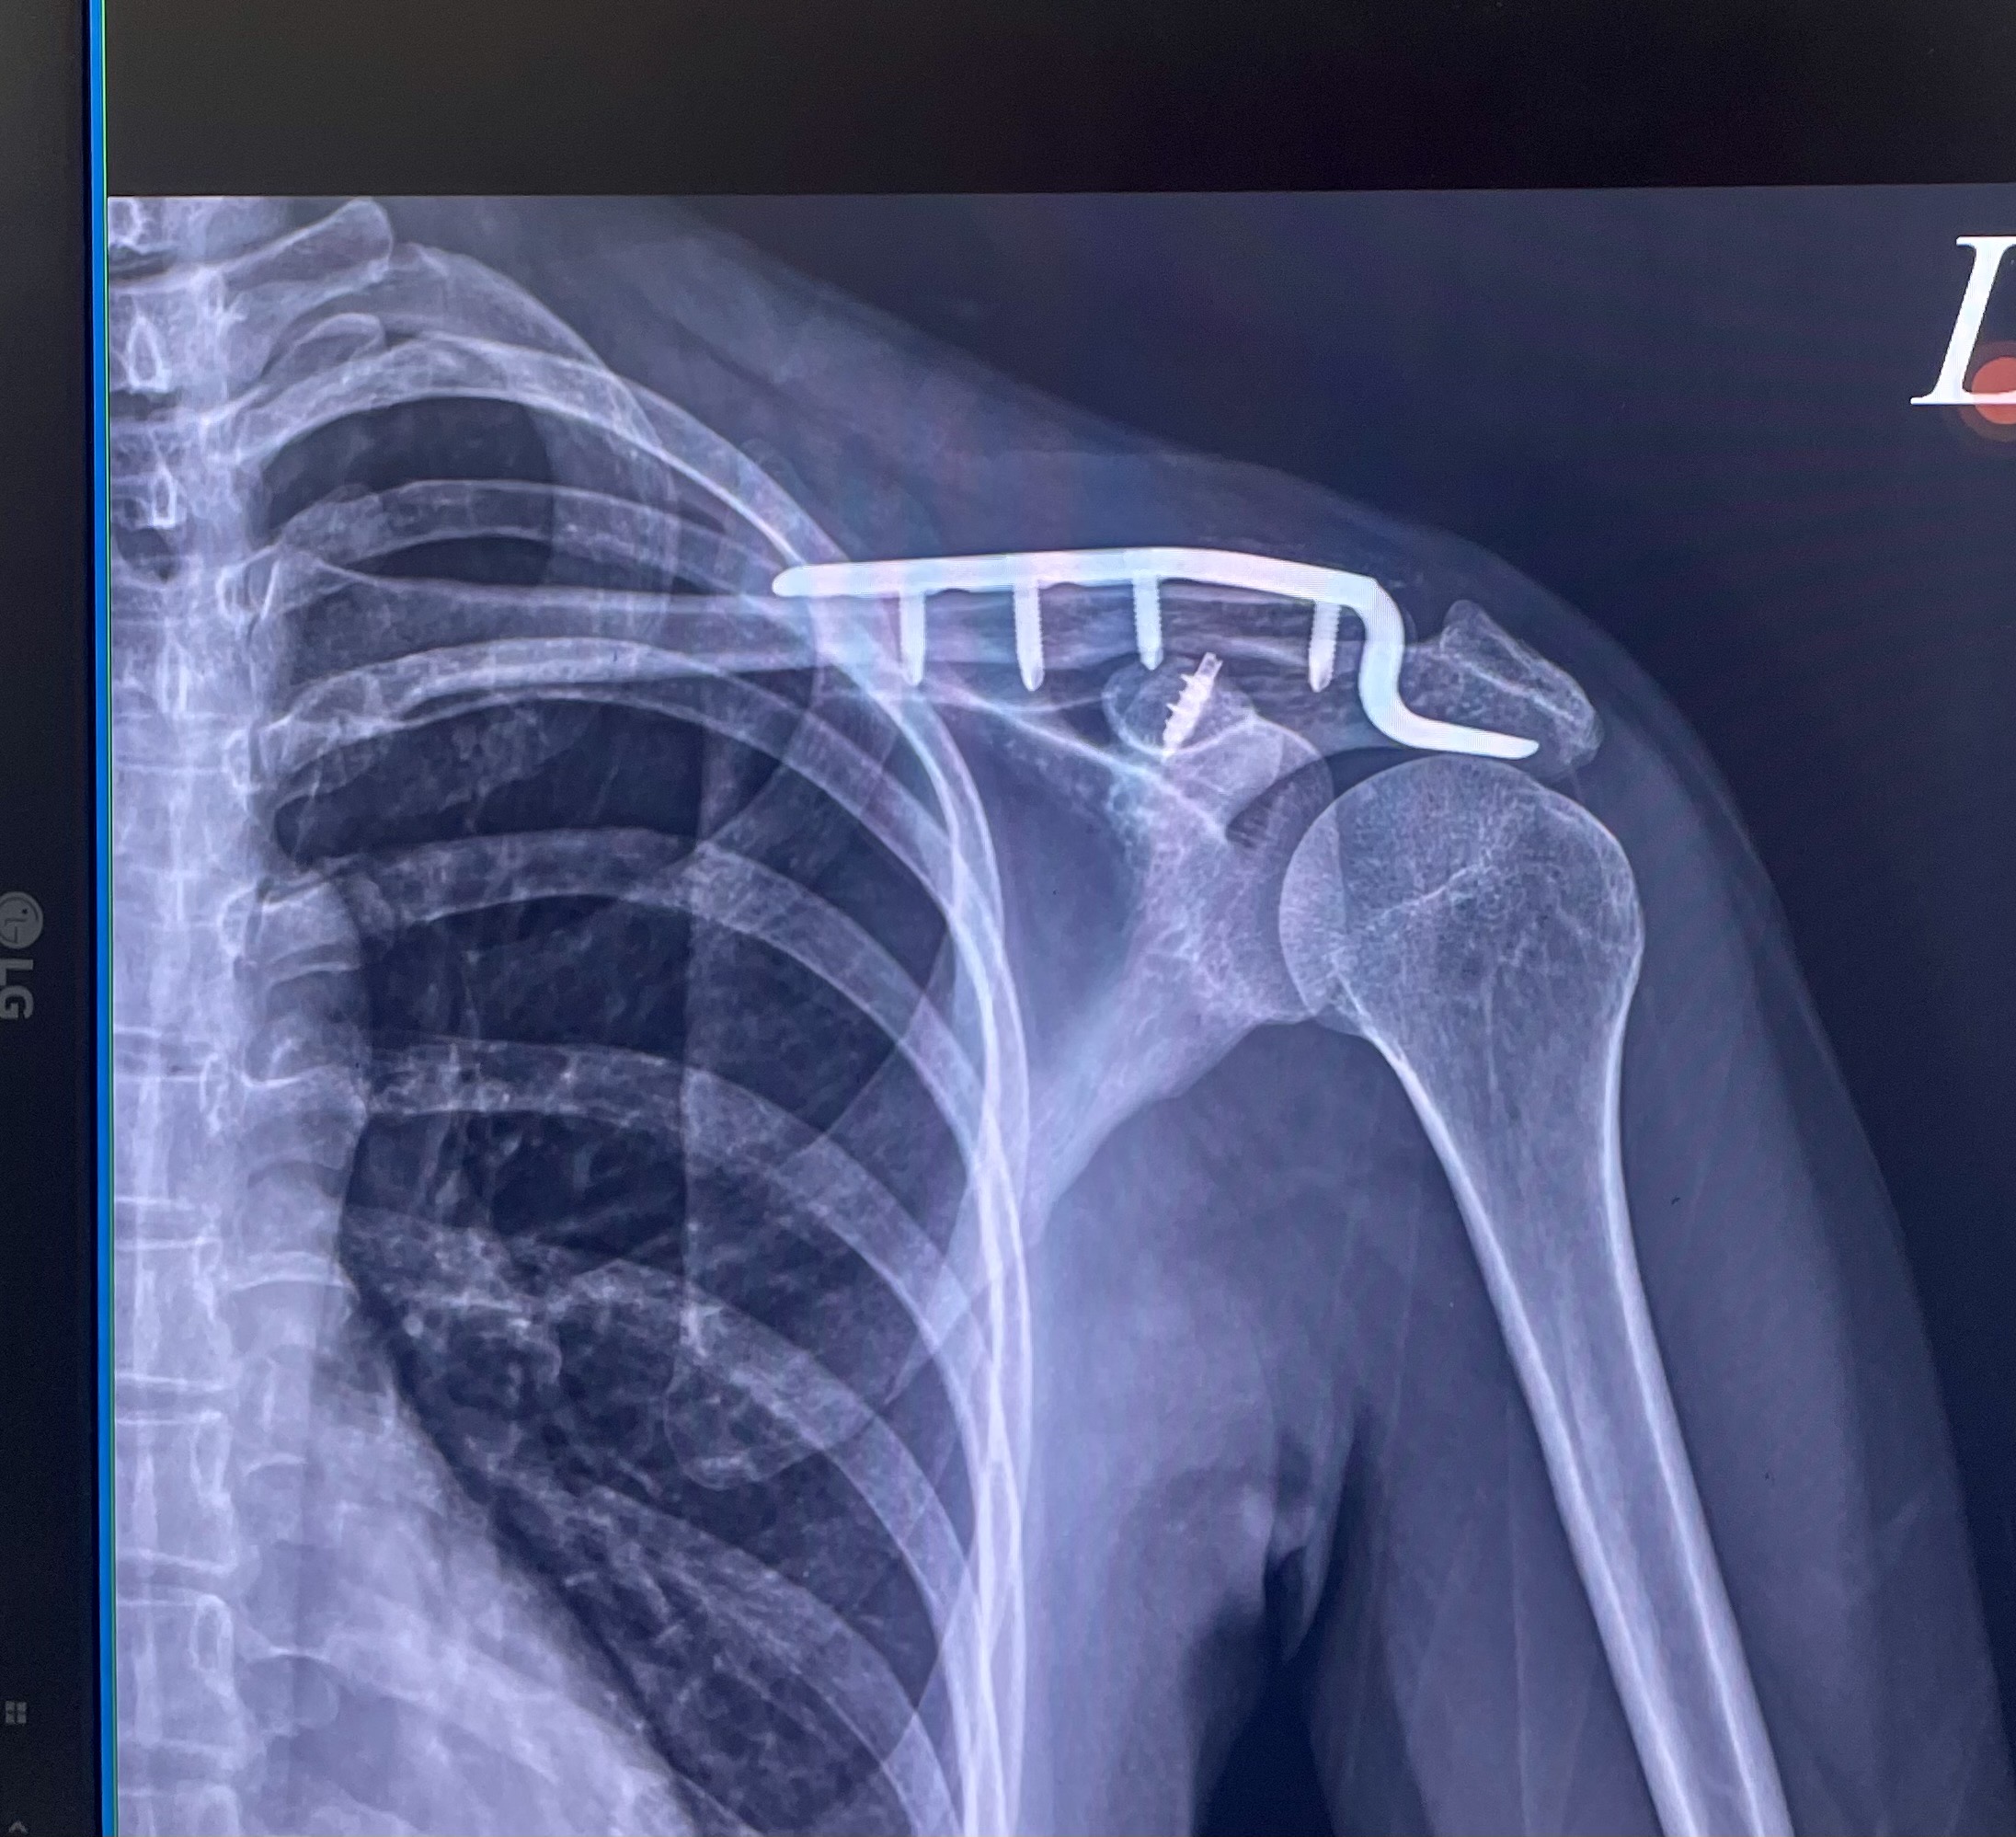

民國 115 年 1 月 17 日,原告楊雅雯(Doris)參加東三塔自行車活動時,被告翁思浩從後方違規切入車道,後輪撞上原告前輪,導致原告摔車,造成左側鎖骨骨折,緊急手術植入鈦金屬骨板,醫囑恢復需一年以上。

左側遠端鎖骨位移性骨折,手術植入鈦金屬骨板,恢復需一年以上

其中特殊材料費(鈦骨板)自費高達 $124,668。另依診斷證明書醫囑「需專人照護約兩個月」,看護費以每日 $2,200 計算共 $132,000。

東三塔自行車挑戰活動,台2線 32.3K。原告左側鎖骨骨折,緊急手術植入鈦骨板。

X光、手術傷口、擦挫傷